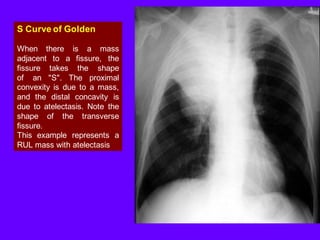

S Curve of Golden

When there is a mass adjacent to a fissure, the fissure takes the shape of an "S". The proximal convexity is due to a mass, and the distal concavity is due to atelectasis. Note the shape of the transverse fissure.

This example represents a RUL mass with atelectasis